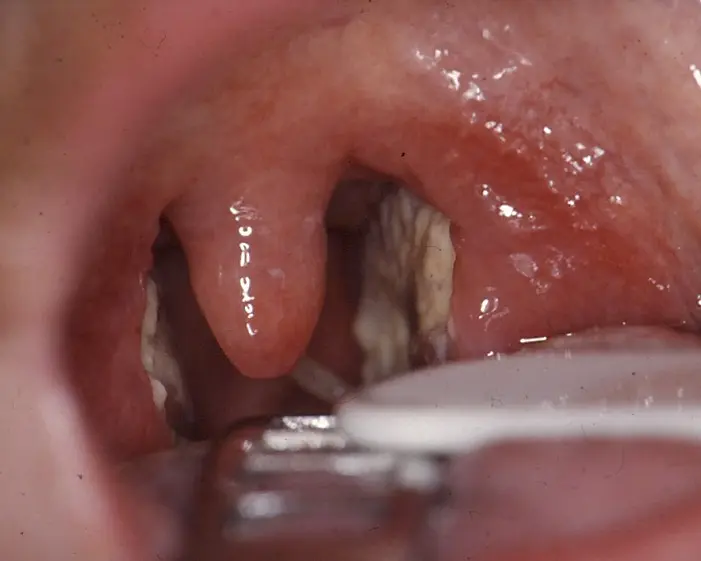

Bei einer Mandelentzündung sind die Mandeln gerötet, geschwollen und oft mit gelblich-weißlichen Eiterflecken bedeckt. Neben Schluckbeschwerden können weitere Symptome wie hohes Fieber, Halsschmerzen, ein unangenehmer Geschmack im Mund und Mundgeruch auftreten.

- Geschwollene Mandeln: Die Mandeln sind gerötet, geschwollen und können mit Eiter bedeckt sein.